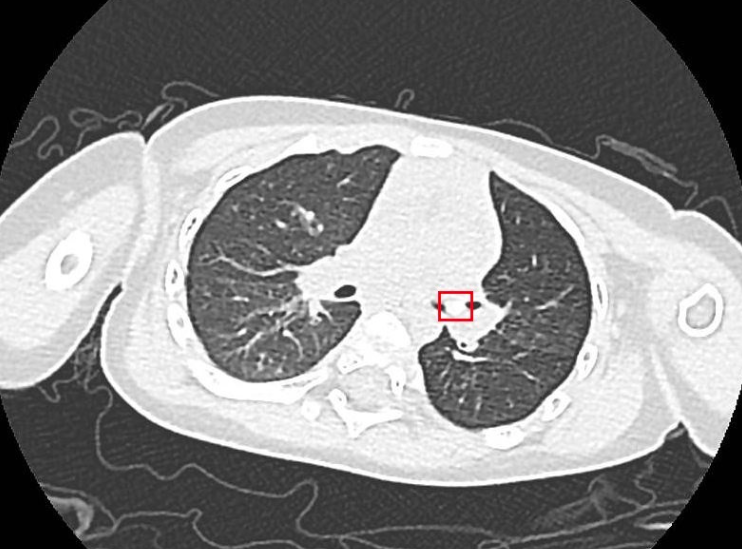

广医二院儿科副主任医师温红艳详细询问了小希的病史,听着她肺部像吹哨子一般高调的声音,感觉很是异常。考虑到小希咳嗽、喘息时间长,原因不明,与家长详细沟通后,医生建议做胸部CT检查。

结果出来了,医生发现在小希的左侧支气管内有一个直径仅为4毫米的异物。小希妈妈想起半个多月前给她喂过一颗葡萄。儿科医生团队讨论后,推测当时小希可能发生过呛咳,异物很可能是一粒葡萄籽!

随后,通过电子纤维支气管镜,医生在小希的支气管中精准找到了异物,用特制的异物钳小心翼翼地夹住后慢慢取出来,果然是一粒葡萄籽。取出异物后,小希咳嗽喘息的症状明显减轻,吃奶和睡觉很快正常了。